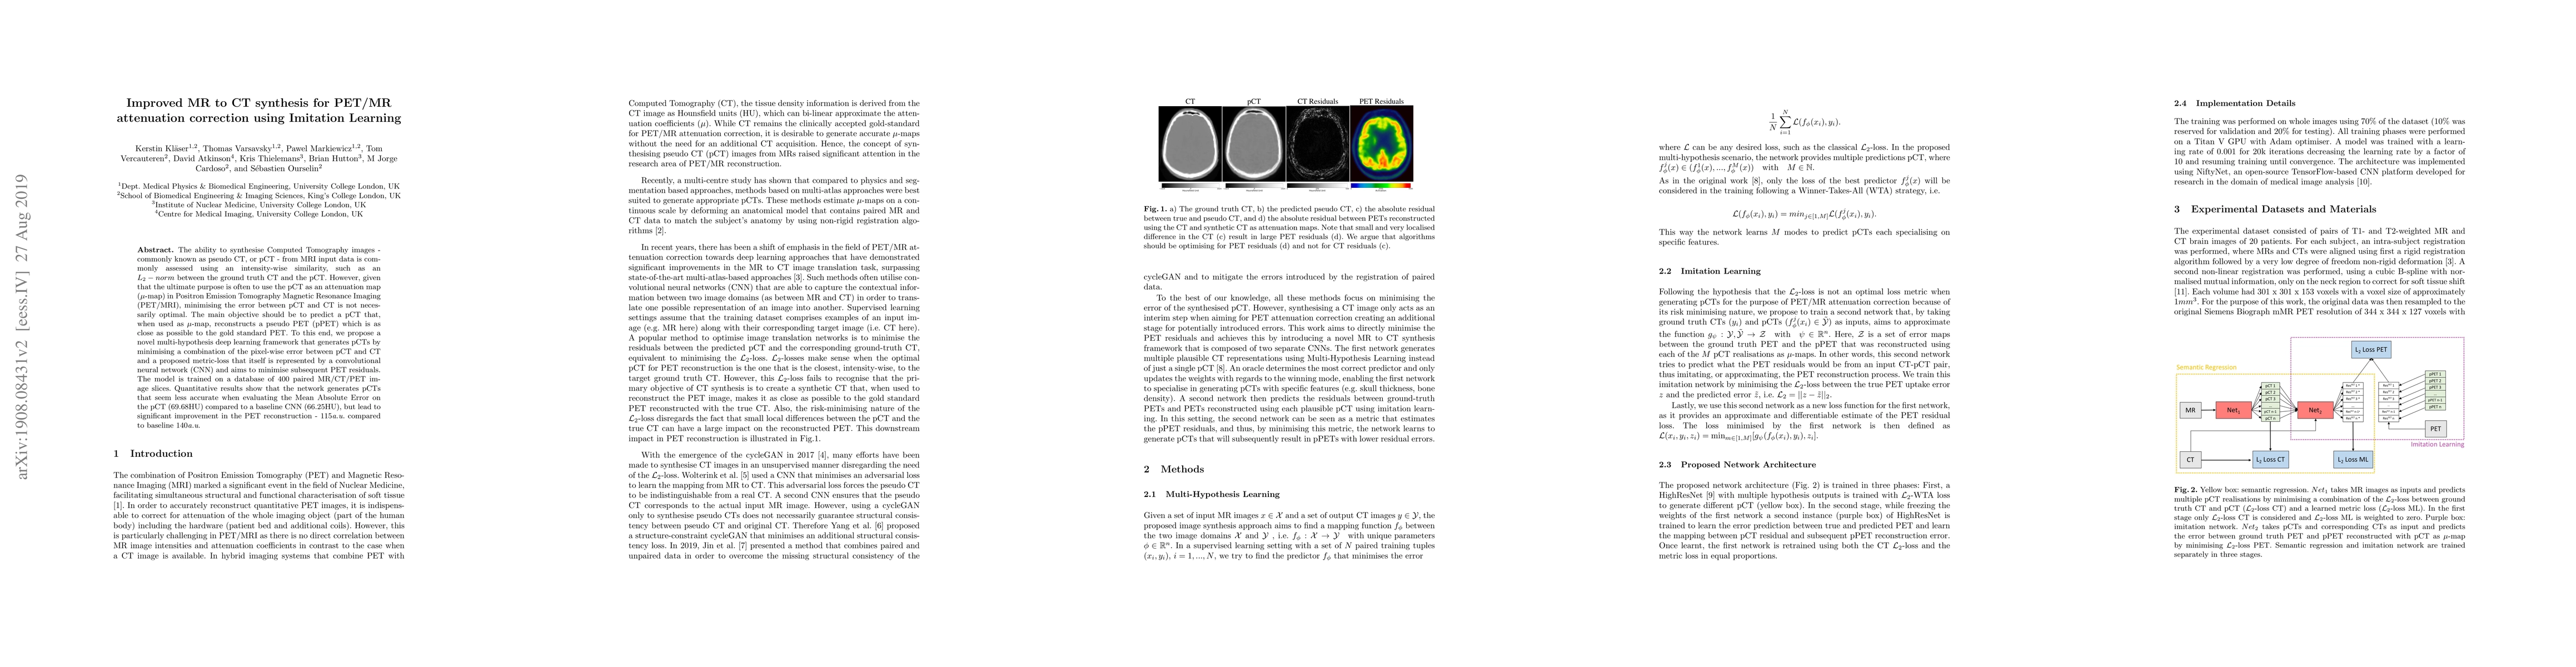

The ability to synthesise Computed Tomography images - commonly known as pseudo CT, or pCT - from MRI input data is commonly assessed using an intensity-wise similarity, such as an L2-norm between the ground truth CT and the pCT. However, given that the ultimate purpose is often to use the pCT as an attenuation map ($\mu$-map) in Positron Emission Tomography Magnetic Resonance Imaging (PET/MRI), minimising the error between pCT and CT is not necessarily optimal. The main objective should be to predict a pCT that, when used as $\mu$-map, reconstructs a pseudo PET (pPET) which is as close as possible to the gold standard PET. To this end, we propose a novel multi-hypothesis deep learning framework that generates pCTs by minimising a combination of the pixel-wise error between pCT and CT and a proposed metric-loss that itself is represented by a convolutional neural network (CNN) and aims to minimise subsequent PET residuals. The model is trained on a database of 400 paired MR/CT/PET image slices. Quantitative results show that the network generates pCTs that seem less accurate when evaluating the Mean Absolute Error on the pCT (69.68HU) compared to a baseline CNN (66.25HU), but lead to significant improvement in the PET reconstruction - 115a.u. compared to baseline 140a.u.